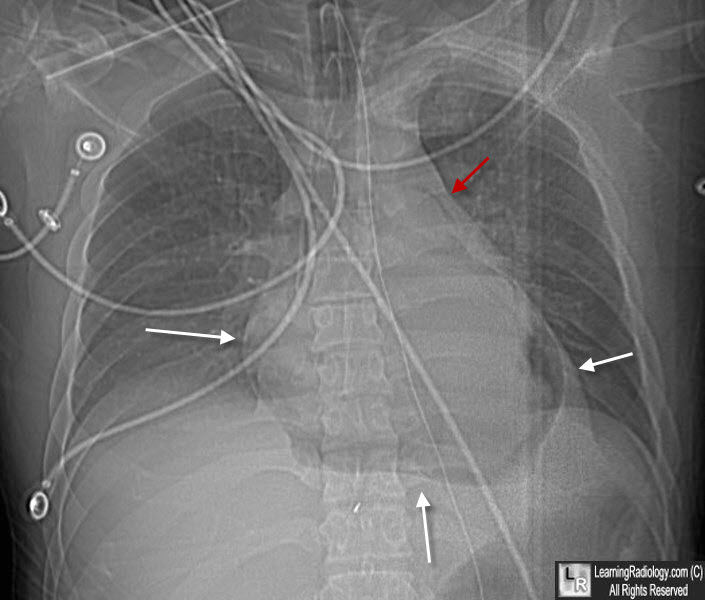

Pneumopericardium. This is the "scout" image from a CT scan of the chest. Notice the halo of air surrounding the heart (white arrows) that does not extended above the level of the great vessels (red arrow). The patient was stabbed in the chest.